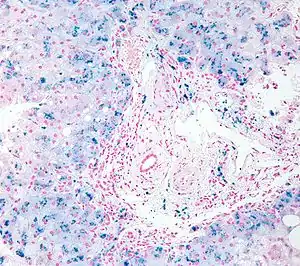

In histology, histopathology, and clinical pathology, Perls Prussian blue is a commonly used method to detect the presence of iron in tissue or cell samples.[1]: 235 [2][3][4] Perls Prussian Blue derives its name from the German pathologist Max Perls (1843–1881), who described the technique in 1867.[2] The method does not involve the application of a dye, but rather causes the pigment Prussian blue to form directly within the tissue.[5] The method stains mostly iron in the ferric state which includes ferritin and hemosiderin, rather than iron in the ferrous state.[6]

Perls's method is used to indicate "non-heme" iron in tissues such as ferritin and hemosiderin,[6] the procedure does not stain iron that is bound to porphyrin forming heme such as hemoglobin and myoglobin.[2] The stain is an important histochemical stain used to demonstrate the distribution and amount of iron deposits in liver tissue, often in the form of a biopsy.[6][7] Perls's procedure may be used to identify excess iron deposits such as hemosiderin deposits (hemosiderosis) and in conditions such as hereditary hemochromatosis.[8] Perls Prussian blue is commonly used on bone marrow aspirates to indicate levels of iron storage[4] and may provide reliable evidence of iron deficiency.[7]

Perls did not publish a detailed procedure other than indicating a dilute potassium ferrocyanide solution was applied to the tissue followed by hydrochloric acid.[2] Ferric iron deposits in tissue (present mostly as ferric iron within the storage protein ferritin) then react with the soluble ferrocyanide in the stain to form the insoluble Prussian blue pigment (a complex hydrated ferric ferrocyanide substance). These deposits are then visualizable microscopically as blue or purple deposits.[9]

Many methods of performing Perls Prussian blue stain for iron have been published, [2] Drury and Wallington (1980) give a protocol that uses a mixture of 1 part 2% hydrochloric acid and 1 part 2% potassium ferrocyanide that is applied to the section for 20–30 minutes followed by a rinse in distilled water and application of a counterstain such as eosin, safranin or neutral red.[5]